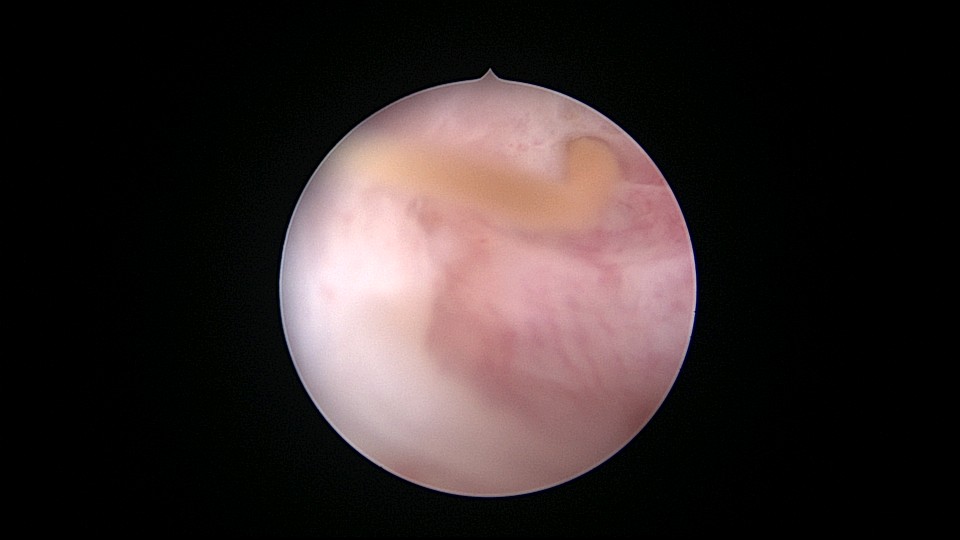

患者55岁,G1P1,顺产1次。安环31年,绝经3年,妇科检查发现宫颈外口息肉,B超宫腔未见分离暗区。子宫前位,宫腔镜见宫颈管下段多发息肉,宫颈内口粘连,宫腔少许淡黄色脓液流出,宫型环位置正常,被镜鞘推挤变形。助手单极电针切除宫颈管息肉时进针过深,引起较多出血,视野不清楚,接手手术,先止血、切除息肉,然后异物钳取出节育环,宫腔无其他异常。病检为宫颈管息肉。